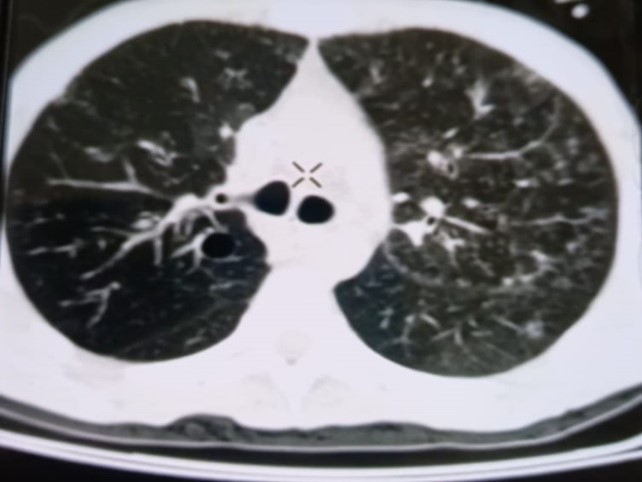

При проведении рентгенологического исследования органов дыхания в динамике спустя 2 недели с момента начала терапии данные компьютерной томографии высокого разрешения указали на следующие изменения: на фоне очаговой диссеминации в легких значительно увеличились по площади участки "матового стекла" в верхних долях обоих легких (описанные зоны неоднородные, сливные); площадь поражения легочной ткани - около 35-40%. В средних и нижних отделах легких с двух сторон выявлялись многочисленные перибронхиальные очаги до 3 мм в диаметре по типу «дерево в почках». В S 6 справа определялась зона альвеолярной инфильтрации. Выпот в плевральных полостях не определялся; внутригрудные лимфоузлы не увеличены. Заключение: признаки двусторонних полисегментарных интерстициально-инфильтративных, диссеминированных мелкоочаговых изменений легких, средняя вероятность вирусной пневмонии (в том числе COVID-19), в сочетании с диссеминированным процессом в легких (рис. 1-4).

Рисунок 1

Рисунок 2

Рисунок 3

Рисунок 4

Рис. 1-4. Компьютерная томограмма пациента Т., с ВИЧ: чередование участков «матового стекла» с диссеминированным процессом, инфильтрацией легочной ткани справа, наличие симптома «дерево в почках» (респираторный бронхиолит).

Учитывая на подозрительные в отношении туберкулеза легких КТ-признаки, пациенту впервые проведена метод ПЦР-диагностики выявления ДНК микобактерий туберкулеза, который показал положительный результат, что позволило установить диагноз «Диссеминированный туберкулез легких, двусторонний. КУМ «-» в сочетании с коронавирусной инфекцией COVID-19 средней степени тяжести, пневмоцистной пневмонией и бактериальной пневмонией» у пациента с ВИЧ-инфекцией 4В стадии. Для дальнейшей терапии пациент был переведен в стационар туберкулезного профиля.